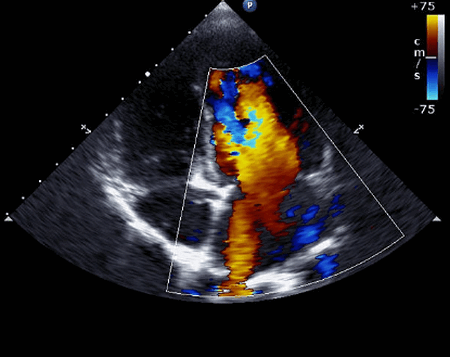

Хотя асимметричная гипертрофия межжелудочковой перегородки обнаруживается на эхокардиографии как самый часто встречаемый тип морфологического рисунка, ГКМП иногда проявляется концентрическим утолщением мышцы верхушки или свободной стенки левого желудочка (ЛЖ). Когда базальная перегородка гипертрофирована и выпячивается, то выводной тракт ЛЖ становится узким, обеспечивая субстрат для динамической непроходимости. При эхокардиографии видно, что скорость потока крови через зауженный выводной отдел ЛЖ увеличивается и создает эффект Вентури. Следовательно, створки митрального клапана и подклапанный аппарат обращается к перегородке (т. е. создается эффект переднего систолического движения), что формирует воспрепятствование сердечного выброса через выводной отдел ЛЖ. Это затруднение является динамичным и зависит от условий нагрузки и размера ЛЖ и его сократительной способности.

Когда аортальный поток прерывается за счет обструкции выводного тракта ЛЖ, развивается преждевременное среднесистолическое закрытие аортального клапана. На эхокардиографии фиксируется переднее систолическое движение передней створки митрального клапана. Это искажает конфигурацию клапана, в результате создается причина для митральной недостаточности. Таким образом, разной степени митральная регургитация почти неизменно сопровождает обструктивный тип гипертрофической кардиомиопатии.